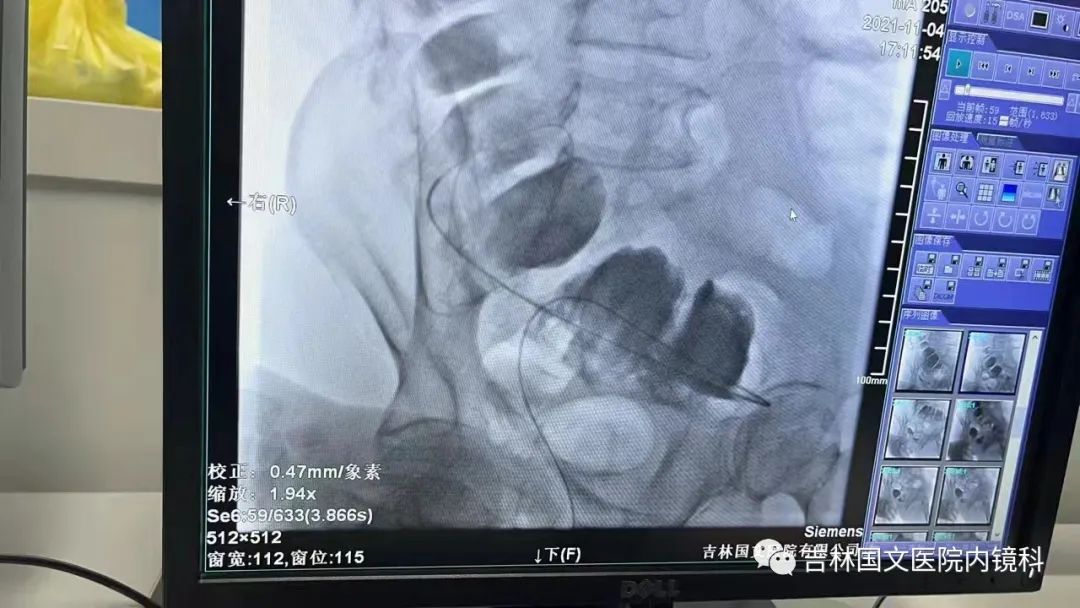

這是一位腸癌的患者,腫物生長在乙狀結(jié)腸,將腸腔堵得只剩一個小孔,糞便自然很難通過,腸梗阻的癥狀使患者十分難受,已多天未排氣排便,患者十分瘦削,開始侯主任未借助任何工具探查一番,結(jié)果就是腸道太迂曲了,實(shí)在無法順利將導(dǎo)絲置入,通過邢主任使用腸鏡在前面引路一直到達(dá)病變部位,這時候侯主任將帶有外套管的導(dǎo)絲從活檢口插入,外套管抵在小孔處,導(dǎo)絲順利進(jìn)入,第一步成功。第二步就是將支架順著導(dǎo)絲送入指定位置,又是一大難關(guān),導(dǎo)絲十分軟,缺乏支撐力,腸道的彎曲十分陡峭,一用力支架抵在腸道低處,患者痛感極強(qiáng),只能另想辦法,嘗試多次后,在兩位主任的豐富經(jīng)驗(yàn)和堅(jiān)持不懈的努力下,支架順利置入,為患者解除了痛苦。